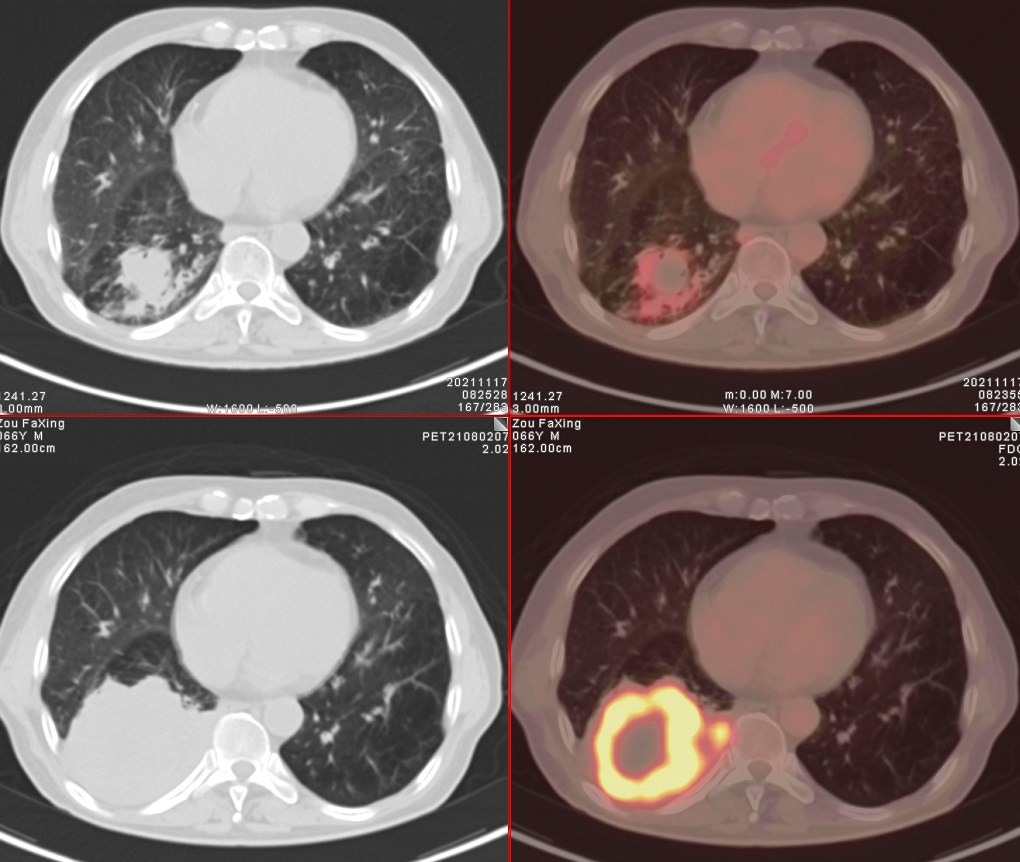

依据影像学分期,该患者后续进行了综合治疗:免疫+化疗+靶向治疗,其中化疗3期,免疫治疗2期及靶向治疗。3个月后患者再次进行了PET/CT检查,对治疗效果进行了评估。2021年11月PET/CT检查结果:

肿瘤病灶明显缩小、实性成分明显减少,肿瘤FDG代谢明显减低,相邻胸膜浸润明显改善,已经没有胸水征象。另外,全身其他部位未见明确转移性病变。

上面两张为治疗后,下面为治疗前

复查后PET/CT诊断:右肺下肺癌综合治疗后,肿瘤病灶明显缩小,FDG代谢明显减低,相邻胸膜未见高代谢病变,考虑肿瘤治疗后疗效显著,仅少量肿瘤活性残留。